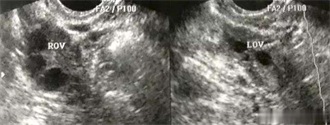

1.B超:通过B超,医生能清楚的观察到卵泡,了解卵泡的大小、形态、生长速度、是否排卵。做一个周期的b超监测排卵就能了解卵泡发育情况,因为卵泡发育是一个连续的过程,所以监测也应该是连续的。一般在月经的第十天开始做彩超监测卵泡大小,然后根据情况安排下次检查时间,一个周期一般需要检查4-5次。发现卵泡直径达到18毫米以后可以安排同房,三四天以后复查彩超,判断是否已经排卵。 肉眼下看到的“泡状体”不仅仅是卵子,还有卵子周围的卵泡液。确切地说,肉眼下我们是看不到卵子究竟长到多少了,除非借助特殊的显微仪器,我们只能通过卵泡的情况间接判断卵子。>>>卵泡监测多少钱?